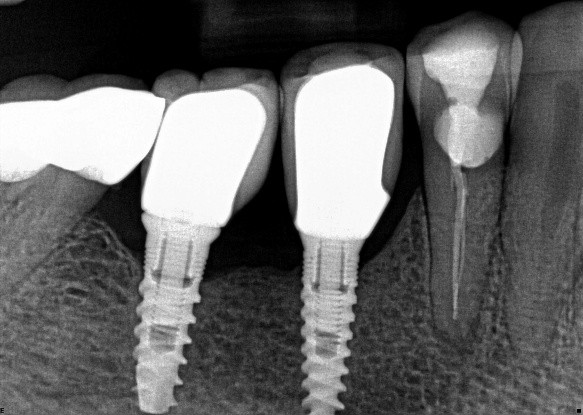

1.  (Select ONE OR MORE correct answers)

What observation(s) can be made for tooth 3.4?